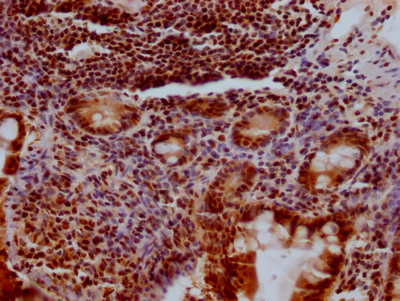

IHC image of CSB-RA194949A0HU diluted at 1:100 and staining in paraffin-embedded human small intestine tissue performed on a Leica BondTM system. After dewaxing and hydration, antigen retrieval was mediated by high pressure in a citrate buffer (pH 6.0). Section was blocked with 10% normal goat serum 30min at RT. Then primary antibody (1% BSA) was incubated at 4℃ overnight. The primary is detected by a Goat anti-rabbit IgG polymer labeled by HRP and visualized using 0.05% DAB.